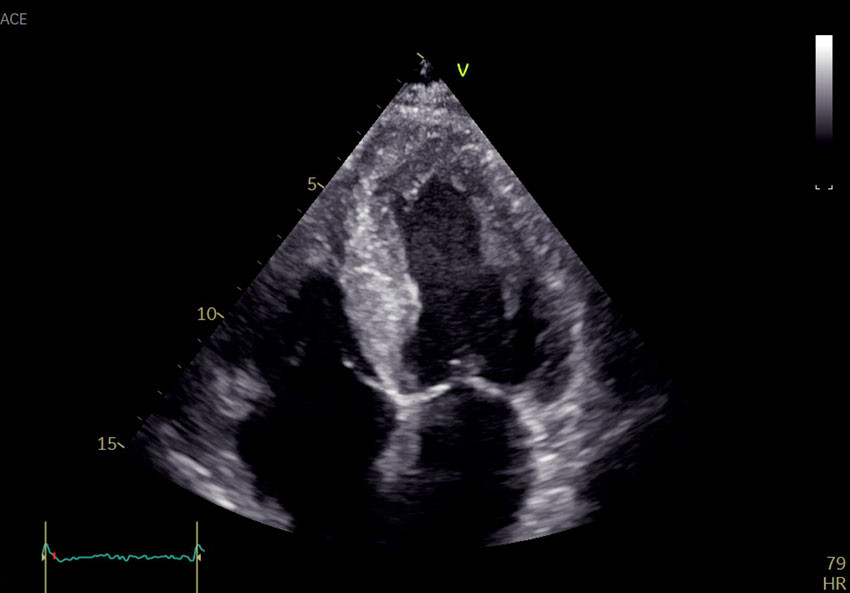

Echocardiography revealed global biventricular hypertrophy with end-diastolic septal thickness of 17 mm (6–10 mm) (Figure 1). There was decreased longitudinal shortening with relative apical sparing. The myocardium had a marked speckled appearance, particularly in the septum. The ejection fraction was 45 % (≥ 52) and the global longitudinal strain was −12 % (−18 to −22). The left atrium was dilated. No significant valve defects were discovered. The patient had no visible pericardial effusion. Coronary angiography was performed the following day and revealed no significant stenoses. Findings of increased wall thickness, speckled myocardium and marked decrease in longitudinal motion with apical sparing raised suspicion of deposition disease, and further investigation was initiated.